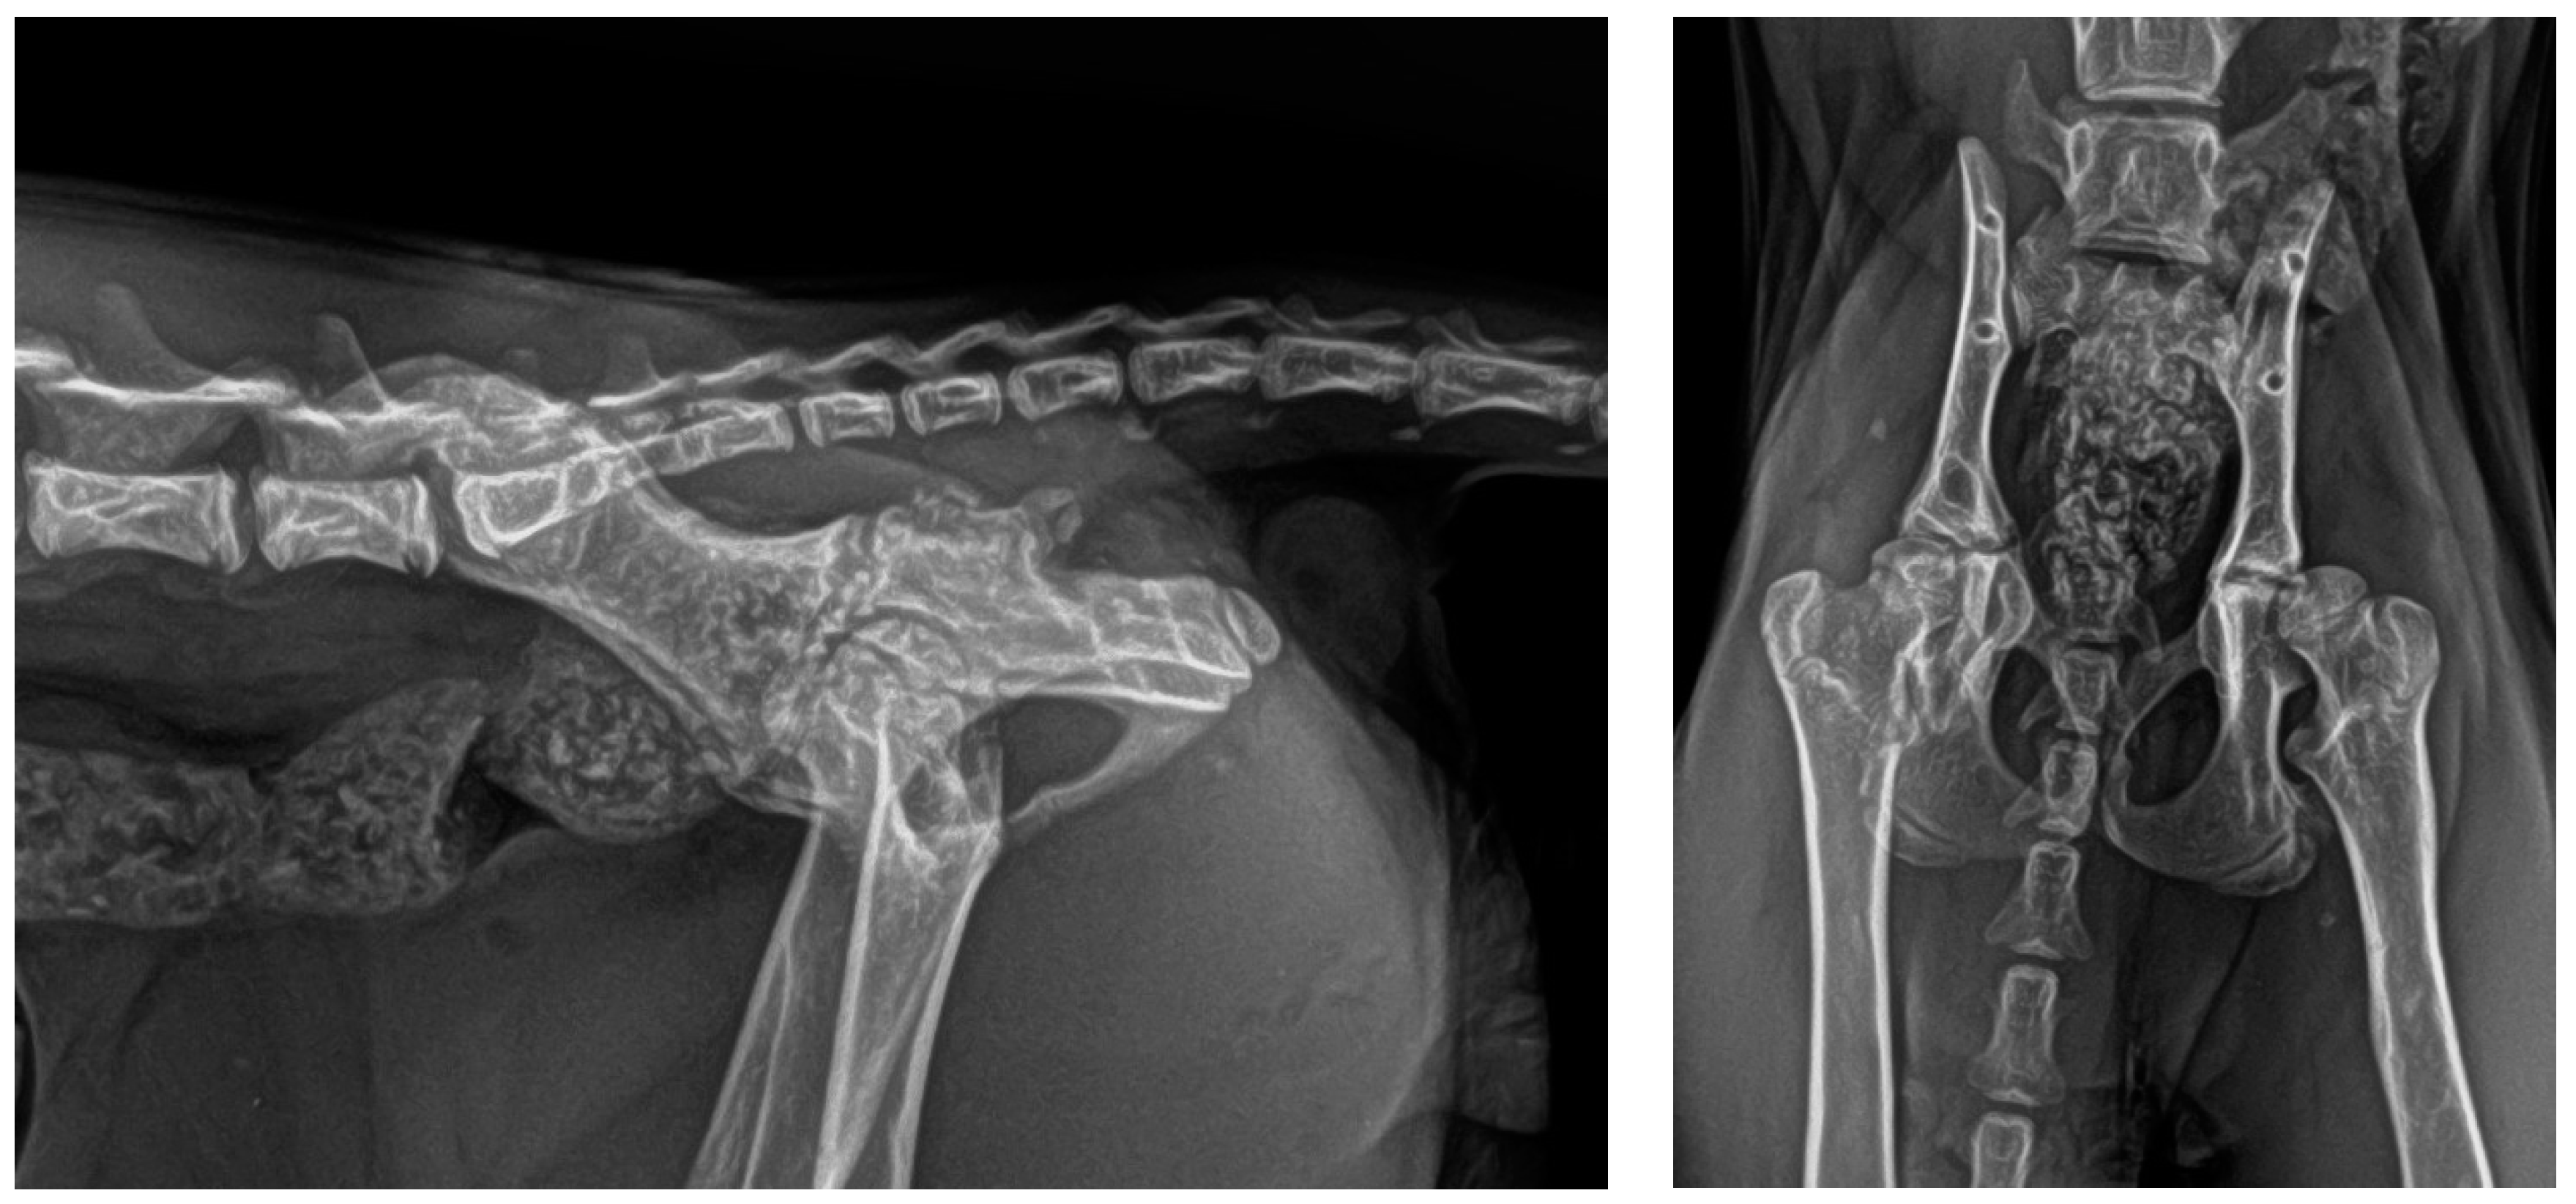

2.3. Postoperative Care

3. Results